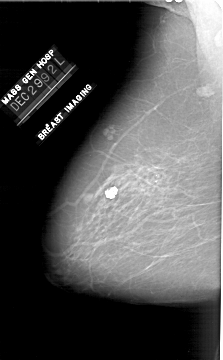

A_1910_1.LEFT_CC

LEFT_CC LINES 6556 PIXELS_PER_LINE 3751 BITS_PER_PIXEL 12 RESOLUTION 43.5 NON_OVERLAY